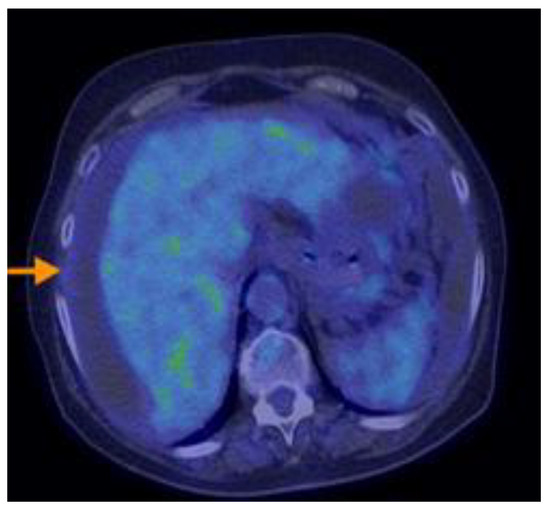

3.2.3. Imaging Findings, Diagnosis, and Differential Diagnosis